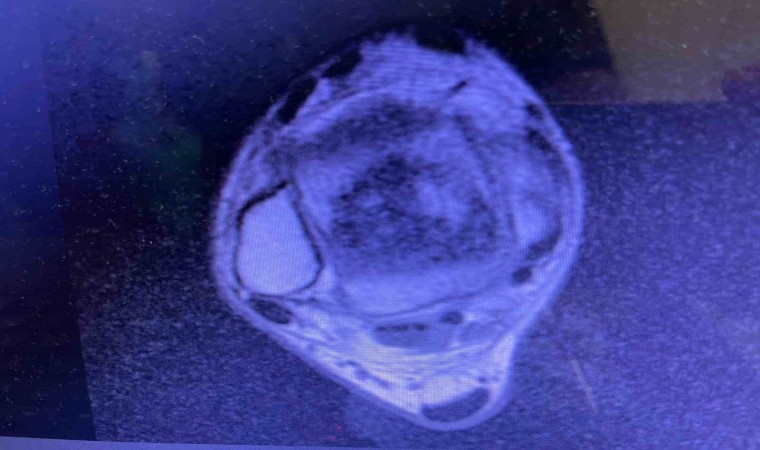

Sağlık alanındaki teknolojik gelişmelerin ve güncel uygulamaların yakından takip edildiği Balıkesir Üniversitesinde gerçekleştirilen ameliyatla ilgili bilgiler veren Ortopedi ve Travmatoloji Anabilim Dalı Öğretim Üyesi Doç. Dr. Aziz Atik; “Lenf kanseri olan 21 yaşındaki hastamız lenf kanseri tedavisi görerek sağlığına kavuşmuş ancak ilerleyen zamanlarda aldığı tedavilerin yan etkisi olarak ayak bileği kemiğinde çürüme meydana gelmiş. Bize başvuran hastamızın eklem yüzeyi bozulmuş ve hastamız yürümekte zorlanıyor, topallıyordu. Büyük bir lezyonu olan hastamıza büyük lezyonlarda uygulanan en iyi tedavi yöntemi olan ve nadir olarak yapılan bir ameliyatla kadavra donörden kemik ve kıkırdak doku nakli gerçekleştirdik.” ifadelini kullandı. Ülkemizde kemik ve kıkırdak bankası olmadığının altını çizen Doç. Dr. Aziz Atik, yurt dışından bir donör bulmak için çalışmalar yaptıklarını ve yurtdışından kemik bulunduğunda ivedi bir şekilde ameliyatı gerçekleştirdiklerini söyledi. Ameliyatın son derece başarılı geçtiğini belirten Doç. Dr. Aziz Atik, güzel bir eklem düzeyi elde ettiklerini ve ameliyatla genç bir insanın topallamadan, ağrısız yürümesini hedeflendiklerini dile getirdi.